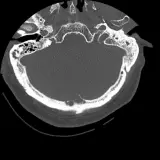

Over 2,100 interactive radiology cases, curated by radiologists for your level of training. Scroll, window, and view cases full screen โ€” just like on PACS. Click linked findings in each writeup to jump straight to them on the image. Cases include sample reports, a focused discussion section, original illustrations, and videos.

Casi completamente interattivi con gli strumenti che ti aspetti su un PACS: scroll, windowing, zoom, pan, misurazioni, ROI e modalitร  a schermo intero.

Annotazioni dettagliate evidenziano i reperti chiave direttamente sui casi. Clicca sui reperti collegati nella descrizione del caso per saltare alla loro esatta posizione sullo scan.